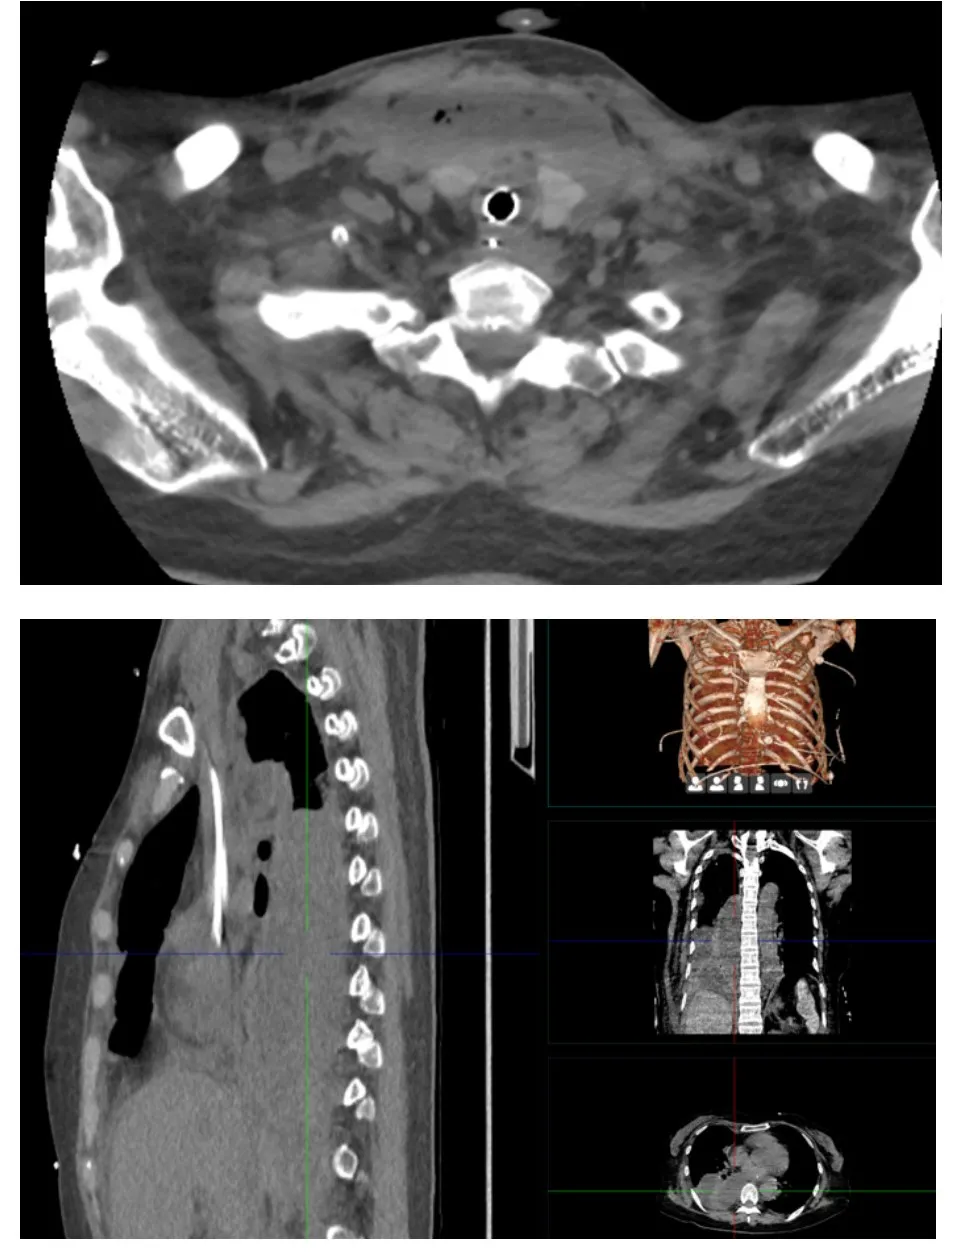

影像学检查显示让人震惊,其颈部、纵膈及胸腔均存在多发脓肿,短期内已引发广泛多部位感染,多器官功能损伤风险极高。当地医院随即启动强化治疗,包括脓肿切开引流、胸腔穿刺引流、血液滤过及强效抗感染方案,但一周后感染仍未控制,家属决定转院。

患者影像学检查结果